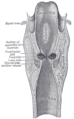

![]() Conducting passages. | |

Laryngoscopic view of interior of larynx. (Trachea labeled at bottom.) | |